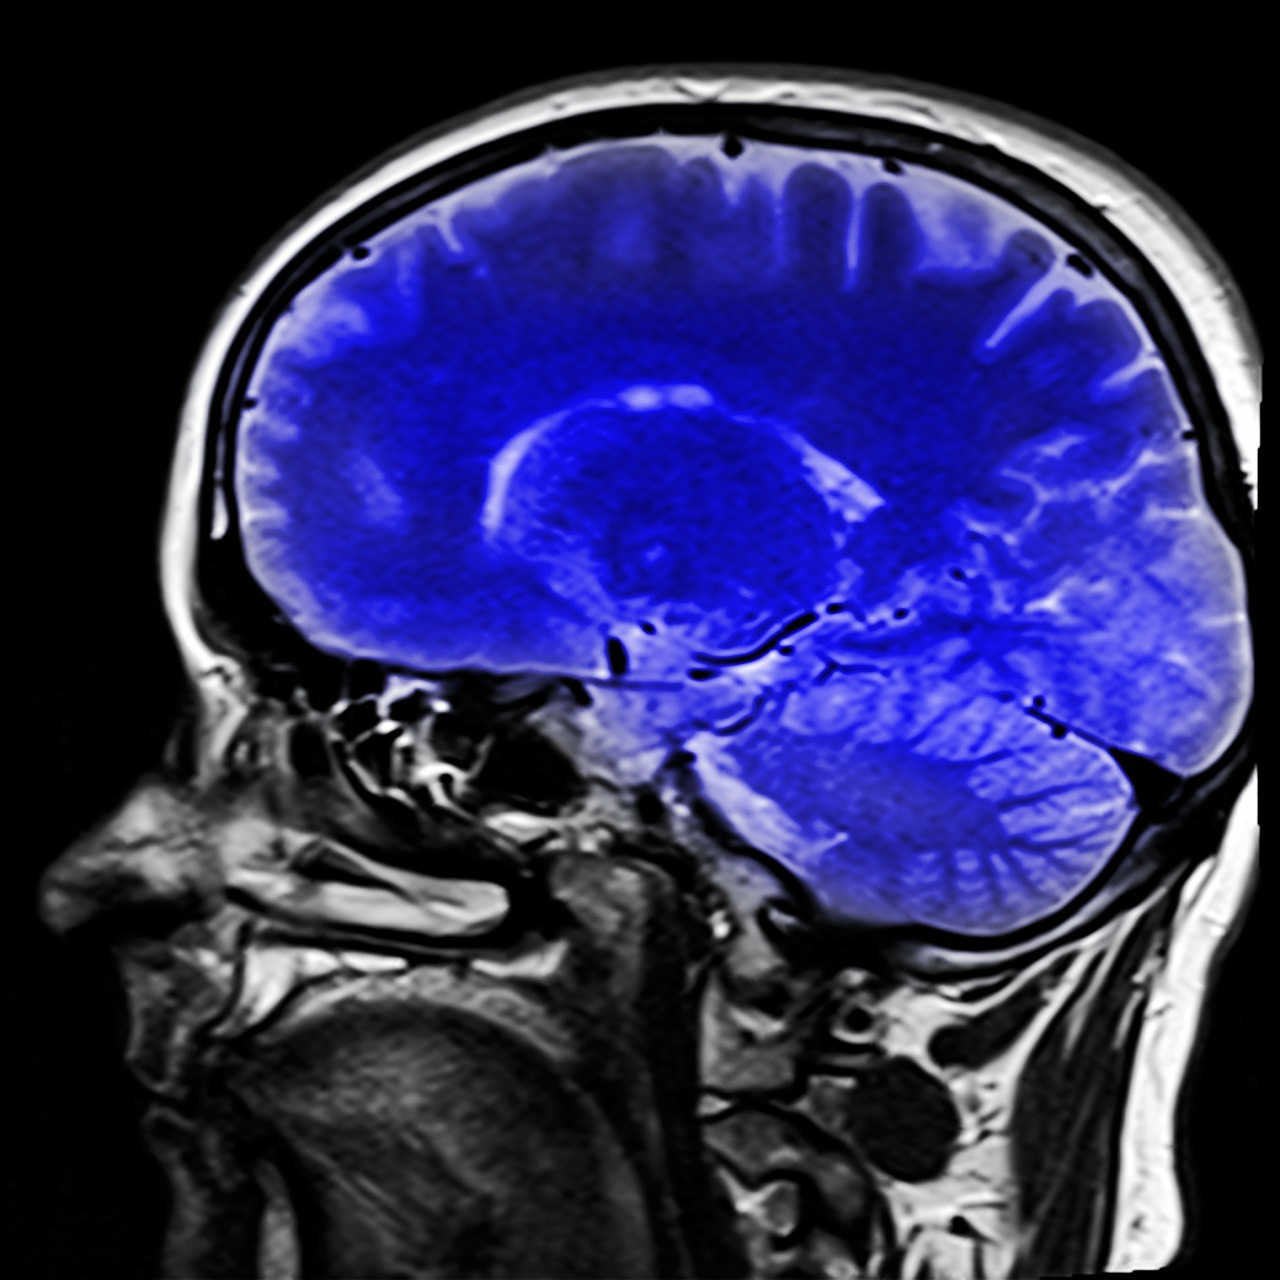

Aunque durante décadas la administración del cannabis medicinal ha estado restringida y controlada por los marcos regulatorios de cada país –lo que ha limitado tanto la investigación clínica como la comercialización de productos para uso medicinal e industrial–, en los últimos años se ha observado un avance significativo a nivel mundial que favorece el uso seguro y la prescripción responsable de cannabinoides. Una de las áreas médicas donde estos beneficios han sido estudiados y analizados de forma importante es en la neurología.

CANNABIS MEDICINAL EN ENFERMEDADES NEUROLÓGICAS

CANNABIS MEDICINAL EN ENFERMEDADES NEUROLÓGICAS

EFECTOS DEL CONSUMO CRÓNICO Y DE USO ADULTO DEL CANNABIS A NIVEL CEREBRAL

EFECTOS DEL CONSUMO CRÓNICO Y DE USO ADULTO DEL CANNABIS A NIVEL CEREBRAL